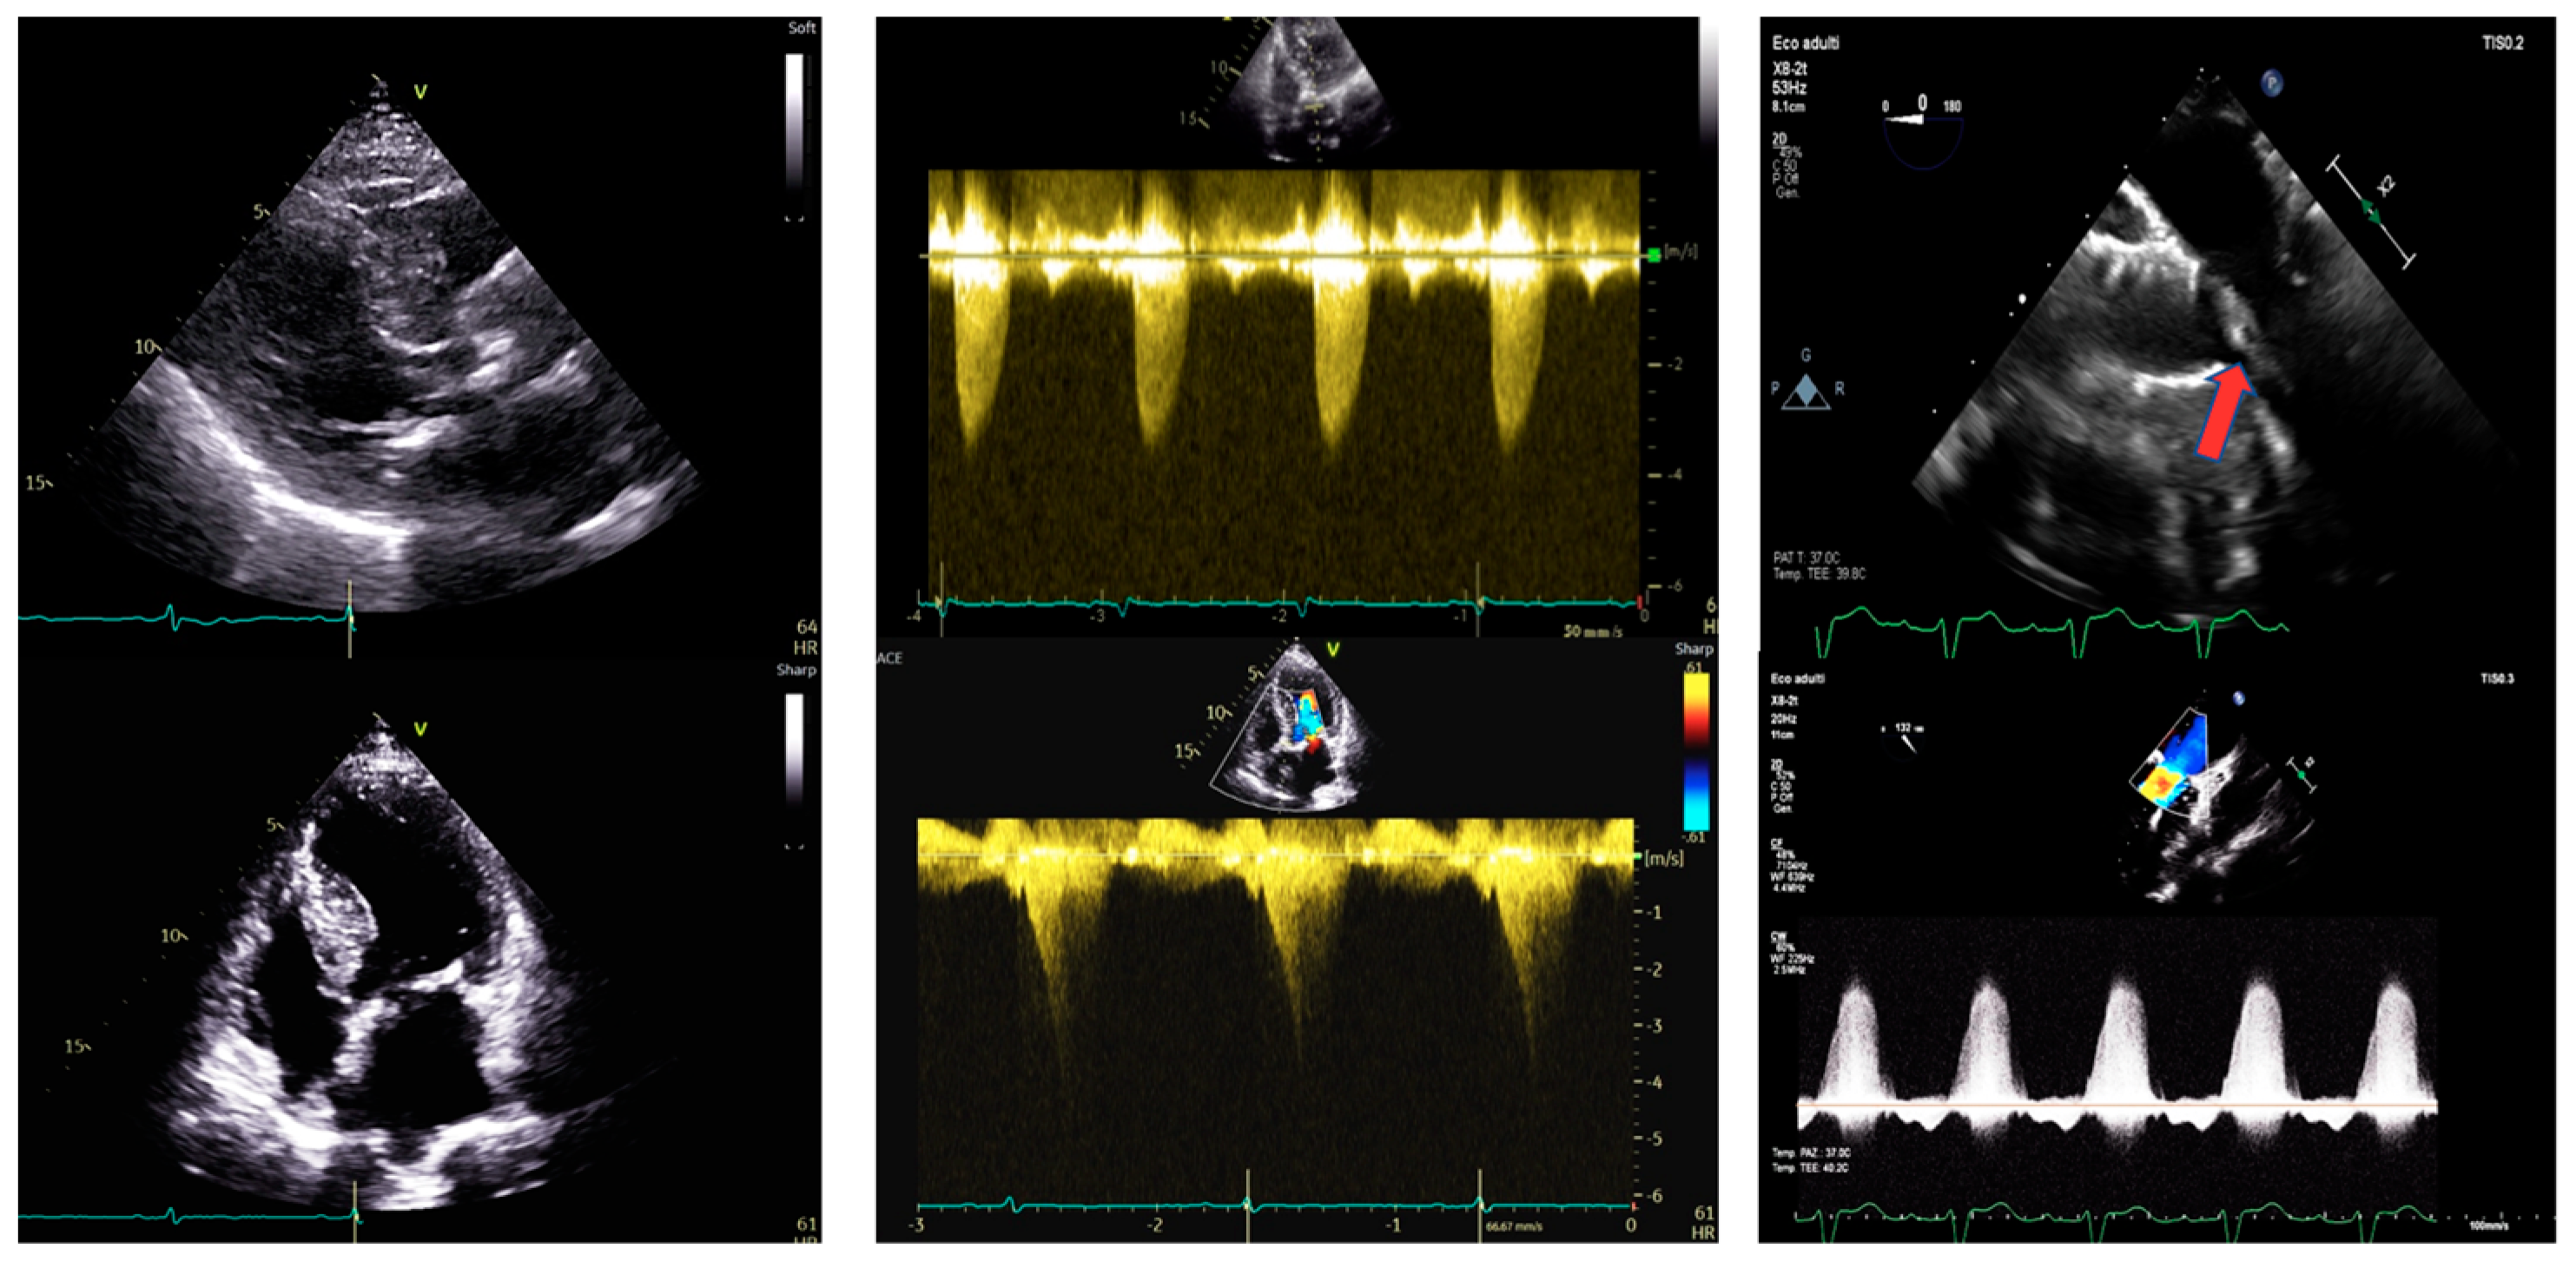

Figure 3. Transthoracic echocardiography of a 79-year-old woman before and after surgical aortic valve replacement and septal myectomy. Left panel. PLAX view (upper) and 4-chamber view (lower). IVS telediastolic diameter = 15 mm; LVEDVi 27 mL/m2. Central panel. Aortic valve peak velocity of 4.5 m/s (upper) with a mean gradient of 51 mmHg and dynamic LVOT gradient (lower) of 42 mmHg after the Valsalva maneuver. Right panel: after cardiac surgery. 4-chamber view (upper) and dynamic LVOT gradient of 11 mmHg (lower) after surgical aortic valve replacement. IVS: interventricular septum. LVEDVi: left ventricular end-diastolic volume indexed. LVOT: left ventricular outflow tract.

After the Heart Team discussion, in consideration of the patient’s age, good overall condition, and acceptable scores (STS 4.2%, and EUROscore II 6%), SAVR and a concurrent surgical myectomy according to Morrow’s procedure were preferred. Post-procedural evaluation showed a residual SAM of the chordal AML with a non-significant LVOT dynamic gradient (10 mmHg), a residual mid-ventricular gradient of 11 mmHg, mild MVR, and a well-functioning aortic bioprosthesis. The patient was discharged home with her current medication regimen, along with antiplatelet therapy and her follow-up has been excellent.

Figure 4. Transthoracic echocardiography of an 80-year-old man before and after aortic valve percutaneous replacement and pacemaker implantation. Left panel. PLAX view (upper) and 4-chamber view (lower). IVS telediastolic diameter = 18 mm; LVEDVi = 54 mL/m2. Central panel. Aortic valve peak velocity of 4.5 m/s (upper) with a mean gradient of 50 mmHg and dynamic LVOT gradient (lower) of 45 mmHg after the Valsalva maneuver. Right panel after TAVI. Increased dynamic LVOT gradient after TAVI (upper) of 65 mmHg after the Valsalva maneuver, which is reduced after pacemaker implantation (lower). IVS: interventricular septum. LVEDVi: left ventricular end-diastolic volume indexed. LVOT: left ventricular outflow tract. TAVI: transcatheter aortic valve implantation.

An 80-year-old man with a known history of OHCM was admitted for severe exertional dyspnea. His genetic testing panel was negative for common genetic variants associated with hypertrophic cardiomyopathy. His medical treatment included beta-blockers and statin due to a history of hypertension and dyslipidemia. TTE revealed HLV (IVS of 18 mm, PW of 10 mm), with hyperdynamic function and an EF of 71%, with no regional wall motion abnormalities. Severe AS was noted with a peak gradient of 81 mmHg, a mean gradient of 50 mmHg, and a planimetric area of 0.6 cm2. SAM of the AML caused a dynamic LVOT gradient of 18 mmHg at rest and 40–45 mmHg after the Valsalva maneuver, with associated moderate MVR. A hemodynamic study showed no coronary artery stenosis and a mid-ventricular gradient of 35 mmHg. The case was discussed in the Heart Team and due to the high STS score (STS score of 6%, and EUROscore II was 7.2%), TAVI was proposed. The patient underwent TAVI with a 29 mm Evolut Pro+ bioprosthesis. Post-procedural TTE showed a residual LVOT gradient of 40 mmHg at rest and 65 mmHg after the Valsalva maneuver, with SAM of AML and mild MVR. Subsequently, due to the onset of a complete atrioventricular block, a dual-chamber pacemaker was implanted. Then, a therapy of increasing doses of oral metoprolol up to 50 mg twice a day resulted in a decrease of LVOTO and improvement of symptoms. The patient is currently doing well, and his follow-up has been excellent.